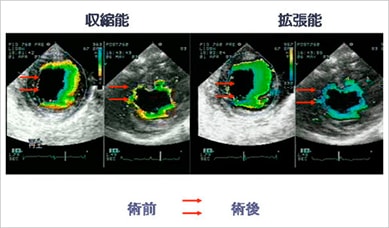

2007年5月、澤氏のチームは拡張型心筋症の患者に対して世界で初めてこの治療法を実施。患者本人の脚から筋肉細胞を抽出して培養した後、直径約4cm、厚さ約0.1mmのシート状にして心臓に張ることで心筋の機能を再生することに成功した。治療前には補助人工心臓を装着し、心臓移植が必要とされていた患者であったが、手術の3か月後には心臓の収縮率が改善し、さらに補助人工心臓を取り外すことができるまでに血液の送出量が回復。その年の12月に患者は退院することができた。